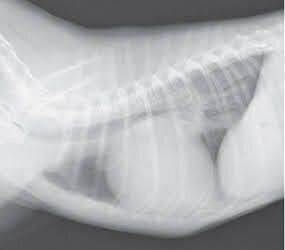

犬の心臓のレントゲン画像

参考・写真/「いぬのきもち」2018年7月号『3号連続企画 犬の死因トップ3を学ぼう!知っておきたい犬の「心臓病」』

• 逆流が認められ、心臓の拡大が認められる。セキなどの症状が認められることがある。

• 心拡大の程度が重度の場合、投薬の開始がすすめられる。また、手術の検討をはじめる時期でもある。

ステージC

• 逆流が認められ、心不全(おもに肺水腫)の状態もしくは以前に心不全になったことがある。

• 必要に応じて利尿薬の追加投与が必要になる。また、手術も推奨される。